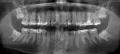

Зуб шестерка нижняя депульпирован и закрыт коронкой, на корне выросла большая киста - один сантиметр. Каналы по снимку запломбированы хорошо, до установки коронки зуб не беспокоил, но сильно разрушился.

Можно ли попробовать лечить или только удаление и имплантация? На какое время рассчитан имплант? Врач говорит, что надо зуб удалять, но мне хотелось бы сохранить свои корни.